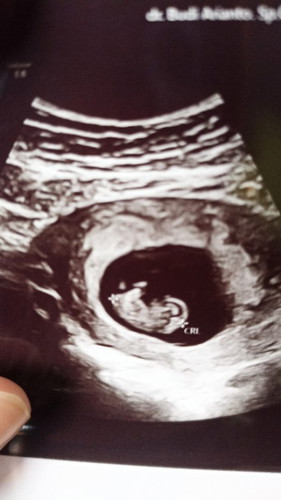

USG dgn Uk janin memang lebih kecil 2mgg

Alhamdulillah MasyaAllah hilang semua rasa penasaran, rasa takut, rasa degdegan 🥺 semoga sehat, tumbuh dan berkembang dgn semestinya dan prosesnya. 2mgg lalu hanya terlihat semua bergumpal ada sedikit tunas, hri ini alhamdulillah bentuk kepala, bentuk tunas kaki sudah mulai terlihat 🥺❤